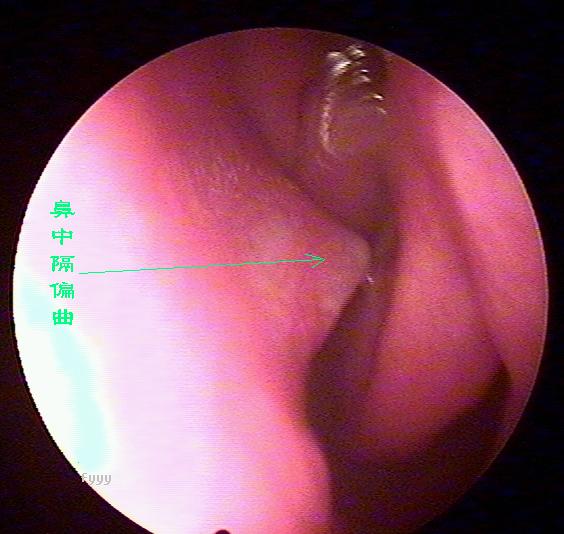

经常流鼻血是鼻中隔偏曲惹的祸

鼻中隔偏曲进行鼻内检查以判断鼻中隔偏曲的类型和程度,注意鉴别鼻中隔粘膜肥厚和是否同时存在鼻内其它疾病,如原发病变—肿瘤、异物或继发病变—鼻窦炎、息肉等。 另一罕见者为鼻中隔梅毒瘤,其质地中亦较硬,但该处粘膜明显充血。